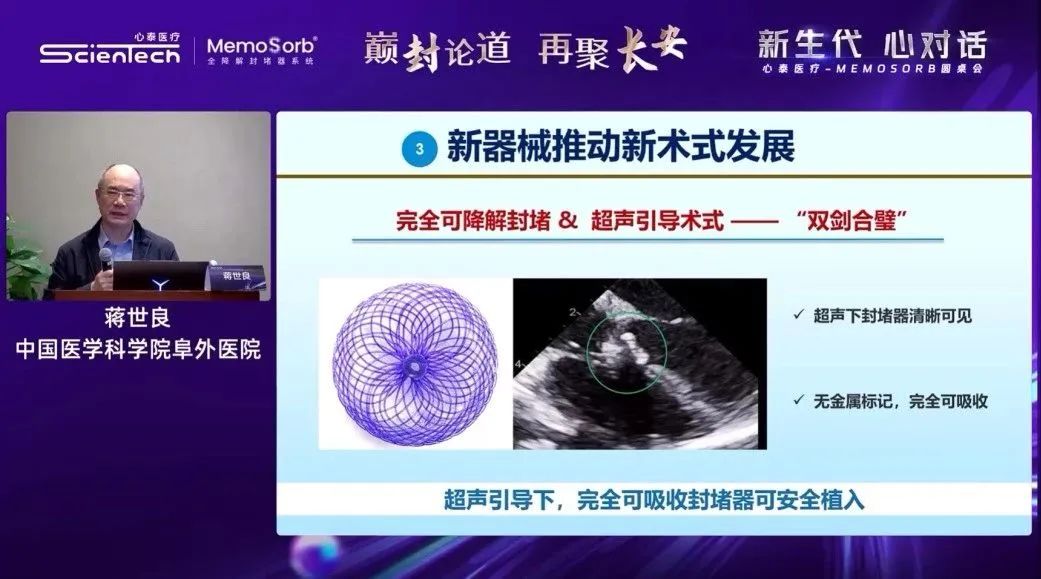

蒋世良教授带来的讲题为《方兴未艾——先心封堵器械发展现状与趋势》,指出,简单先心病的介入治疗是必然趋势,并已经成为目前简单先心病治疗的首选和主流治疗手段,而介入治疗技术的进步发展离不开器械的迭代创新。当下新型全降解封堵器临床应用的持续开展,正在将先心介入治疗带入可降解时代,未来“植入无残留”的健康理念必将造福更多先心病患者。

随后,张玉顺教授以《得心应手——全降解封堵器经皮介入封堵操作技巧》为题,详细介绍了全降解封堵器经皮介入封堵的操作技巧及要领,强调了全降解封堵术“5S”操作法的重要性,明确指出术中超声下封堵器使用的形态变化及评估要求,以保障封堵有效性及安全性。

秦永文教授指出,相较于传统金属封堵器,全降解封堵器植入术的主要不同之处在于全降解封堵器的选型、装载;其次,由于可降解材料在射线下不显影,因此超声影像技术在全降解封堵术中起着至关重要的作用;另外,不同于金属封堵器,全降解封堵器的专利成型锁定设计,使封堵器成型稳定,紧贴心室壁,防脱落,提高了封堵安全性。